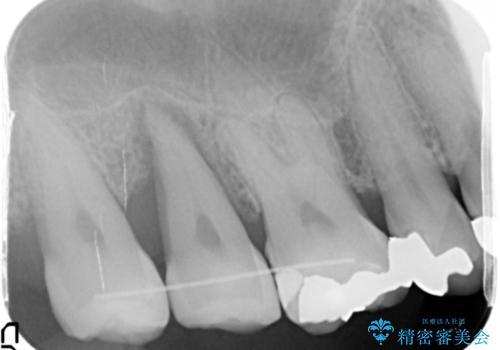

精査したところ、右上の奥歯(右上7)はう蝕が深く骨吸収も進行しており保存不可能な状態でした。

金属アレルギーの疑いがあり、インプラントも避けたいとの患者様のご希望により、親知らずを移植することにしました。

移植がうまくいかない可能性を考慮し、ブリッジもできるよう隣の親知らず(右上8)は残し、反対側の親知らず(左上8)を移植しました。